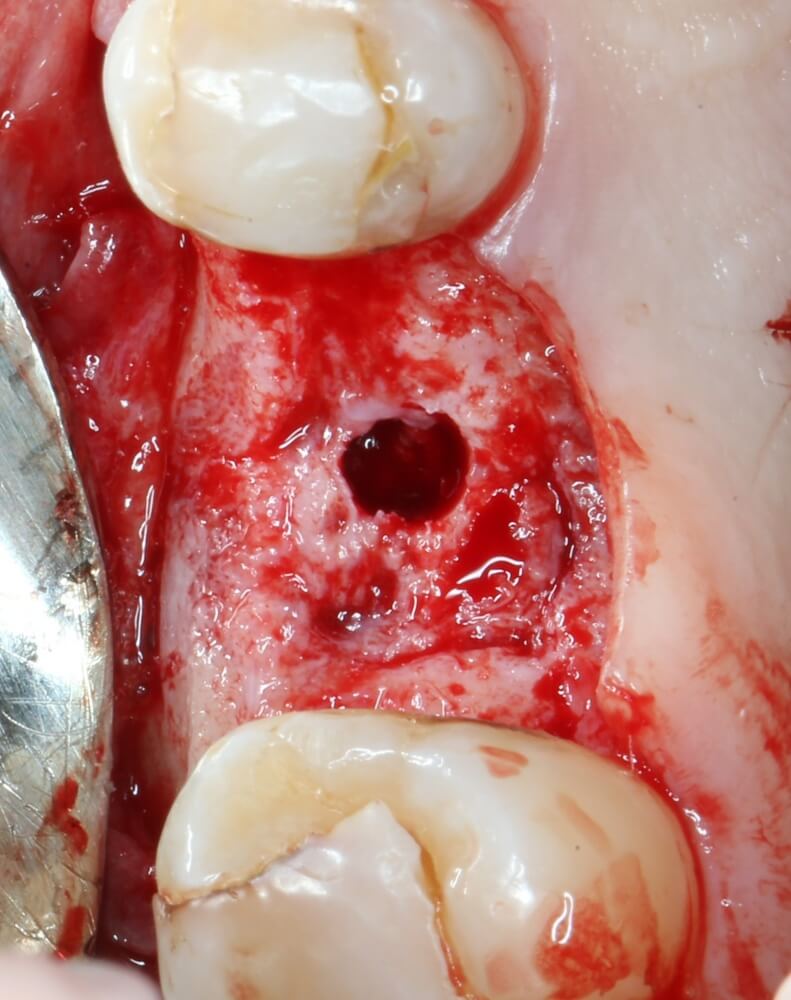

Начинаем подготовку лунки под имплантат

Первым инструментом из хирургического набора является шариковый бор. Он нужен для того, чтобы разметить положение имплантата:

Многие доктора (и некоторые производители имплантационных систем) заменяют шариковый бор в хирургическом наборе на фрезу Линдеманна или пику. На самом деле, шарик намного удобнее, поскольку не заклинивает в плотной кости, может работать любой поверхностью, а его основная функция — поставить точку на поверхности альвеолярного гребня, через которую потом пройдёт ось имплантата. Так что совсем уж углубляться шариком в кость не нужно. Тем более, не стоит проходить им всю глубину будущей лунки. Поставили точку — и всё на этом.

Далее, мы проходим лунку на всю глубину пилотной фрезой диаметром 2.0 мм.

Следующей мы используем фрезу 2.0/3.2:

Такие фрезы — особенность имплантационной системы Astra Tech. Они нужны для того, чтобы не разломать края лунки и сделать переход между фрезами (а мы переходим с 2.0 на 3.2 мм) более точным и плавным, благодаря направляющей 2.0 мм. Однако, пройти лунку такой фрезой на всю глубину удаётся далеко не всегда. В таких случаях используется обычная спиральная фреза диаметром 3.2 мм (с зеленой полоской). Но в нашем случае такой необходимости нет, ибо выше только субантральное пространство, поэтому мы работаем только вот такой двойной фрезой.

После этого можно еще раз (последний, кстати), проверить направление и ангуляцию оси будущего имплантата. Всё тем же вышеозначенным пином: